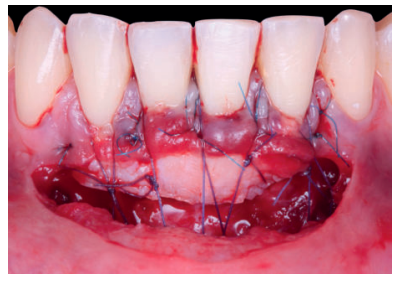

Una vez creado el lecho receptor, se procedió a la obtención de un ITC de la mucosa masticatoria palatina y a la sutura de dicho injerto mediante dos puntos colchoneros horizontales, uno situado en la parte mesial y otro en la parte distal del sobre. Para mayor adaptación y estabilización de las papilas se realizó un punto suspensorio cogiendo papila e ITC, mediante sutura de 6/0 no reabsorbible (Figura 3).

También, se realizó una sutura dentosuspendida para asegurar el injerto en posición apical, este punto se ancló en el periostio apical al injerto y suspendido alrededor de la cara lingual del diente con recesión mediante sutura de 5/0 reabsorbible. Se dejó cicatrizar por segunda intención en la base (zona de la vestibuloplastia).

Previamente a la intervención, la paciente se enjuagó durante un minuto con un colutorio de clorhexidina. La técnica quirúrgica comenzó con la preparación del lecho receptor, se realizaron incisiones intrasulculares a nivel cervical hasta la línea ángulo de todos los dientes del frente antero-inferior (33-43), desinsertando la base de la papila sin seccionarla con la ayuda de instrumentos de tunelización. Posteriormente se realizó una incisión en el fondo de vestíbulo (Figura 11). A continuación, se obtuvo un injerto de tejido conectivo del paladar introduciéndolo en el lecho receptor, siendo todas las suturas realizadas de la misma manera que en el caso clínico 1, usando tanto material reabsorbible como no reabsorbible de 5/0 y 6/0 ceros (Figura 12).